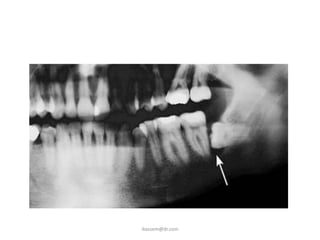

C. Periodontal Disease

• Erupted teeth adjacent to

impacted teeth are

predisposed to periodontal

disease.

• As it decrease amount of bone

on the distal aspect of adjacent

2nd molar, with deep

periodontal pocket on the

distal aspect of the 2nd molar.